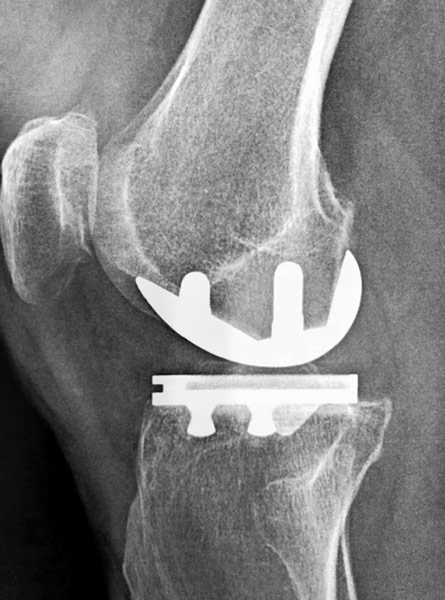

Douleur + raideur + boiterie. Homme 75 ans, opéré du ligament croisé antérieur 40 ans auparavant. On propose une prothèse totale du genou. Rééducation immédiate, récupération en 4 mois sauf complication.

Prothèse totale du genou NexGen (société Zimmer) à glissement, cimentée au fémur, au tibia et à la rotule, plateau polyéthylène fixe, postéro-stabilisée.